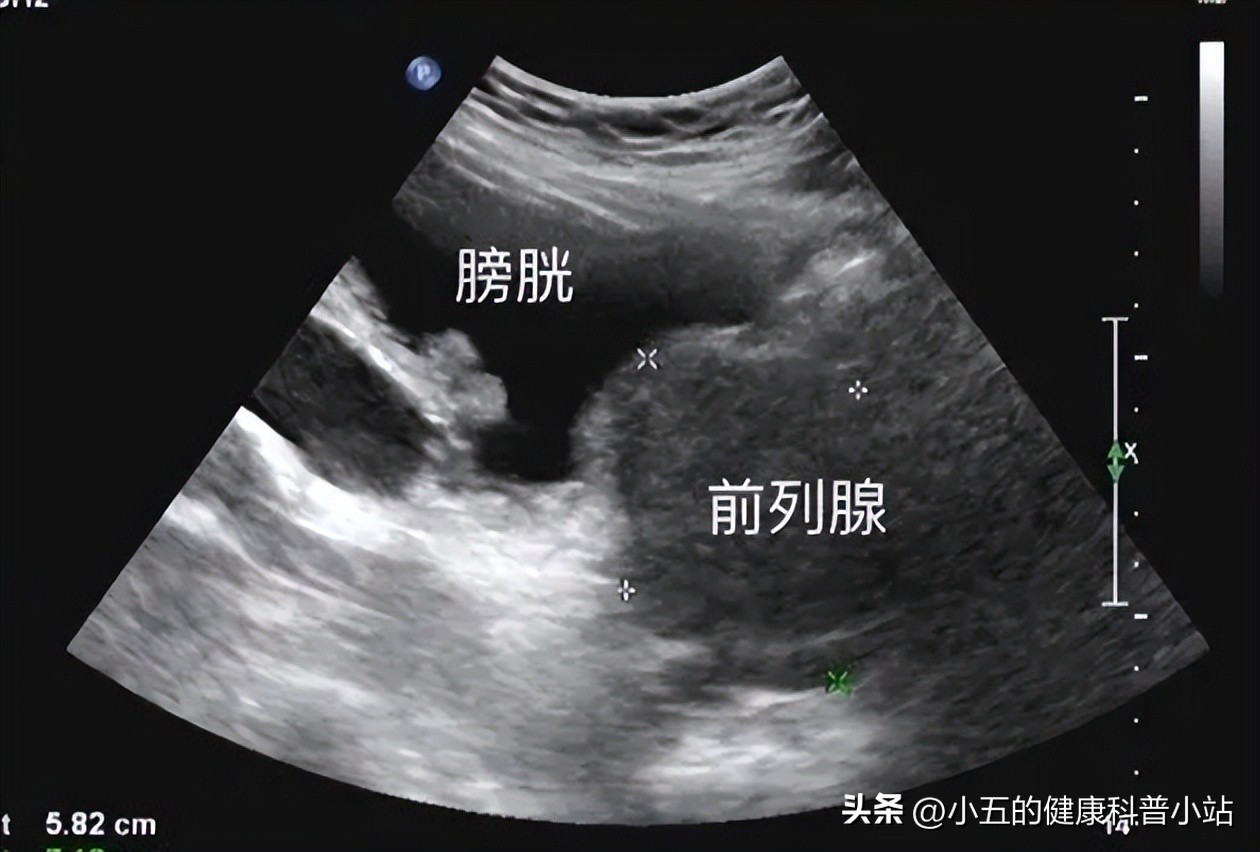

From inf.news

What is increased nocturia?What is the relationship between increased Increased Nocturia This becomes more common as we grow older. Nighttime urination is likely excessive if you. Nocturia can lead to sleep deprivation, daytime fatigue, impaired concentration, depression, and a loss of productivity, so it's important to bring it to your healthcare. This is most common in people over the age of 60. Nocturia refers to getting out of bed at night. Increased Nocturia.